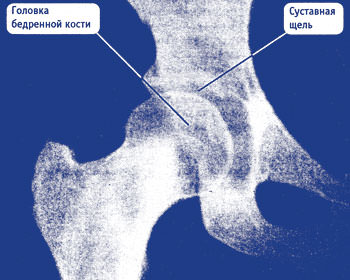

Чтобы увидеть, в чем заключается разница сустава в норме и больного, нужно понимать, что показано на снимках при коксартрозе.

Головка сустава имеет правильную форму: округлую и ровную. Суставная щель в норме. Так выглядит здоровый сустав бедренной кости.

Неквалифицированный специалист при таком снимке может поставить коксартроз. Но боли могли быть вызваны грыжей или защемлением.